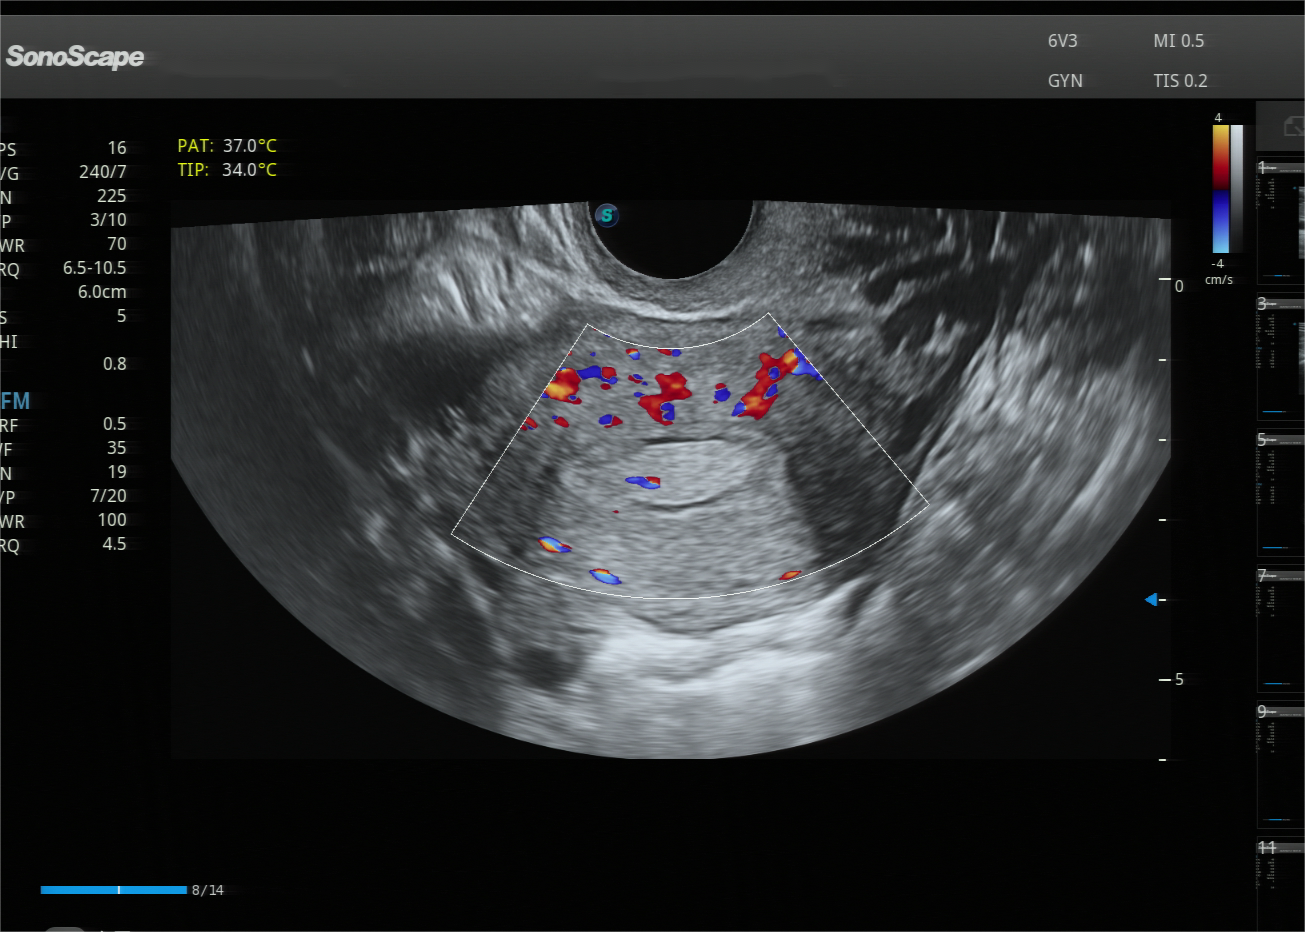

该院妇科副主任江晓婧接诊了李女士,在详细询问病史及体格检查后,为其开具了经阴道超声检查。超声医学科医师胡晓丹为李女士进行了二维彩超检查,结果发现宫腔内见一高回声区、边界清晰、回声均匀,为了进一步明确病灶位置、形态等,张晓燕在与李女士沟通并取得同意后,采用宫腔三维彩超进行检查,清晰地观察到宫腔左侧中上段有一个约1.8cm*0.9cm*1.2cm的团块样回声,考虑为子宫内膜息肉,为妇科医疗团队提供宫腔镜手术“路线图”。

超声医学科主任施唯介绍,子宫内膜息肉是子宫腔内局部内膜过度生长形成的良性赘生物,大小从几毫米到几厘米不等,其表现多为子宫出血、不规则月经、中老年人可出现绝经后出血,部分患者可能有下腹隐痛、白带异常,甚至还可能影响胚胎着床。子宫内膜息肉约三分之一患者可能没有任何症状,仅在体检行经阴道超声时偶然发现,经阴道超声,是首选的筛查方法。常规经阴道二维超声可发现息肉,但宫腔三维超声能立体成像、清晰显示息肉的大小、数量、位置等,为宫腔镜手术精准定位、完整切除提供精准依据。